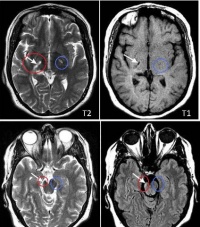

偏瘫[编辑 | 编辑源代码]

同一侧上肢及下肢肌肉瘫痪称为偏瘫。有时伴有同侧下面部肌肉及舌肌的瘫痪。自大脑皮质运动区开始经内囊、脑干至脊髓前角细胞之间的神经径路的任何部位病变,均可产生偏瘫,起病隐袭,呈缓慢进行性发展的偏瘫,病因多为颅内占位性病变,如脑肿瘤、脑脓肿、颅内血肿、脑寄生虫等,如表现为脊髓特点的进行偏瘫其病因多为脊髓肿瘤、脊柱结核、脊柱增生性病变、肥厚性硬脊膜炎等。突然起病,急速发展的偏瘫多由脑血管病引起。主要为一侧上下肢的运动障碍。在临床上有四种表现形式:①意识障碍性偏瘫:表现为突然发生意识障碍,并伴有偏瘫,常有头及眼各一侧偏斜。②弛缓性偏瘫:表现为一侧上下肢随意运动障碍伴有明显的肌张力低下,随意肌麻痹明显面不随意肌则可不出现麻痹,如胃肠运动、膀胱肌等均不发生障碍。③痉挛性偏瘫:一般的是由弛缓性偏瘫移行而来,其特点是明显的肌张力增高。上肢的伸肌群及下肢的屈肌群瘫痪明显,肌张力显著增高,故上肢表现为屈曲,下肢伸直,手指呈屈曲状态,被动伸直手有僵硬抵抗感。④轻偏瘫:在偏瘫极轻微的情况下,如进行性偏瘫的早期,或一过性发作性偏瘫的发作间隙期,瘫痪轻微,如不仔细检查易于遗漏。